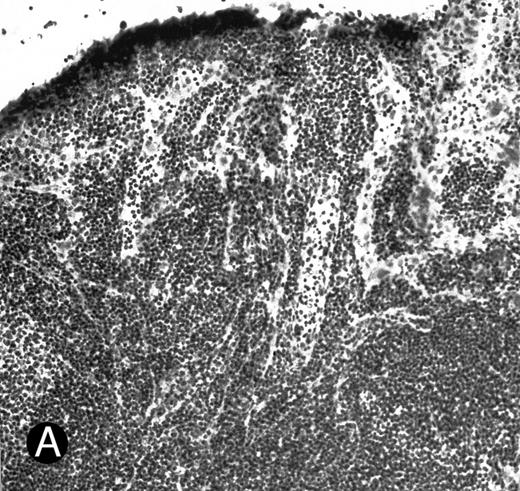

WEHI78/24 cells were preincubated with hybridoma supernatants and their binding to HEV in normal and inflamed PLN was assessed. As previously reported5 and reproduced here, WEHI78/24 cells failed to bind normal lymph node HEV, but WEHI78/24 cells bound well to HEV following CFA-induced inflammation (Figs 1 and 2). MoAb L11, but not class-matched, binding negative control MoAbs, blocked binding of WEHI78/24 cells to inflamed HEV by greater than 70% (Fig 2). For comparison, the effects of anti–L-selectin, αL, αM, β2, and α4 MoAbs, as well as two cell binding isotype matched control MoAbs (RB6-8C5 and 30G12), are presented in Table 1. None of the MoAbs used in these assays caused aggregation of WEHI78/24 cells.

WEHI78/24 cells bind to inflamed, but not normal PLN HEV. Binding of WEHI78/24 cells to normal (A) and CFA-inflamed (B) PLN HEV was assessed in modified Stamper-Woodruff frozen section assays. WEHI78/24 cells were added to freshly cut frozen sections and incubated for 30 minutes at 5°C under constant rotation. Nonadherent cells were washed away and the sections fixed and stained with thionine as described.14 A lower magnification of the normal lymph node is shown to illustrate lack of binding on multiple HEV.